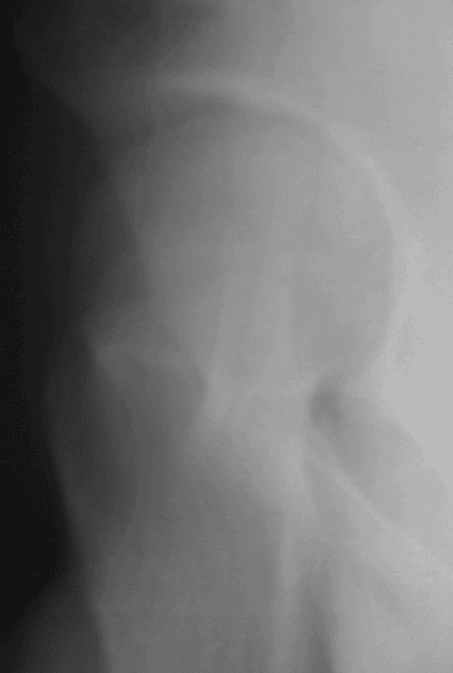

Скорее это все же фрагмент ацетабулярного края, хотя это должно быть хорошо видно на КТ,а "не видно",надо смотреть возможно другие срезы, в боковой пр. головка не изменена.

Несколько соображений к "картинкам". На прямом снимке и КТ-томограммах все типичные линии вертлужной впадины: крыша, передняя стенка, задняя стенка - сохранены. На КТ-сканах 6 и 7 появляется фрагментация головки. С учетом R-томограмм отломок расположен спереди-снизу, а не сзади-сверху от сустава, как написано в описании КТ.